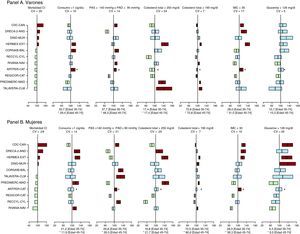

ResultadosSe incluyó a 28.887 participantes. Los factores de riesgo cardiovascular más prevalentes fueron: hipertensión arterial (el 47% en varones y el 39% en mujeres), dislipemia con colesterol total ≥ 250 mg/dl (el 43 y el 40%), obesidad (el 29% en ambos sexos), tabaquismo (el 33 y el 21%) y diabetes mellitus (el 16 y el 11%). El colesterol total ≥ 190 y ≥ 250 mg/dl presentó el coeficiente de variación mínimo y máximo, respectivamente (el 7-24% en varones y el 7-26% en mujeres). La concordancia media en las determinaciones lipídicas entre laboratorios fue excelente.

En la Tabla 2 se presentan por sexos los valores de glucemia, presión arterial y las prevalencias de glucemia basal alterada, diabetes mellitus e HTA diagnosticada y real. Independientemente del diagnóstico de diabetes mellitus, las mujeres de CDC, DINO y HERMEX presentaron una prevalencia de glucemia basal ≥ 126 mg/dl significativamente superior a la media (Figura 1). Independientemente del diagnóstico de HTA, la prevalencia de presión arterial sistólica ≥ 140 mmHg o diastólica ≥ 90 mmHg era significativamente superior a la media en ARTPER, CDC y CORSAIB en ambos sexos, y en los varones del estudio RIVANA y las mujeres de RECCYL y TALAVERA (Figura 1).

Figura 1. Mortalidad por cardiopatía isquémica estandarizada por la población europea por comunidad autónoma y razón estandarizada de prevalencia (desviación porcentual media con el intervalo de confianza del 95% de las desviaciones porcentuales) de consumo de tabaco de 1 o más cigarrillos/día, presión arterial sistólica ≥ 140 mmHg o diastólica ≥ 90 mmHg, colesterol total ≥ 250mg/dl y ≥ 190mg/dl, índice de masa corporal ≥ 30, glucemia basal ≥ 126 mg/dl. En los estudios componentes se compara cada factor de riesgo con la prevalencia global en el estudio DARIOS (del 100% indicada por la línea vertical) por orden de mortalidad cardiovascular poblacional. Al pie de cada factor se muestra la prevalencia media del factor correspondiente para dos grupos de edad (35-74 años y 45-74 años). CI: cardiopatía isquémica; Cig: cigarrillo; CV: coeficiente de variación; IMC: índice de masa corporal; PAD: presión arterial diastólica; PAS, presión arterial sistólica.

La prevalencia de obesidad, sobrepeso, perímetro de la cintura alterado y tabaquismo se detalla en la Tabla 3. Los estudios ARTPER, CDC, DRECA-2 y HERMEX presentaron una prevalencia de obesidad significativamente superior a la media en varones y mujeres (Figura 1). El tabaquismo presentó poca variabilidad entre estudios, particularmente en varones. Aun así, los participantes masculinos de ARTPER, CORSAIB y HERMEX y las mujeres de DRECA-2, HERMEX, PREDIMERC y RIVANA eran significativamente más fumadores que la media (Tabla 3 y Figura 1).

La prevalencia de dislipemia real varió notablemente entre colesterol total o cLDL y con el punto de corte elegido (Tabla 4). La Figura 2 muestra la distribución del colesterol total y sus fracciones en varones y mujeres. En HERMEX, PREDIMERC y TALAVERA en varones y DRECA-2, HERMEX y PREDIMERC en mujeres, la prevalencia de dislipemia (colesterol total ≥ 250 mg/dl) fue significativamente superior a la media (Figura 1). Con el punto de corte de colesterol total ≥ 190 mg/dl, la variabilidad entre estudios se reducía considerablemente. Aun así, los estudios HERMEX, PREDIMERC, RIVANA en varones y mujeres y TALAVERA en varones y DINO en mujeres presentaron prevalencias significativamente superiores a la media de DARIOS.

La prevalencia de factores de riesgo cardiovascular en población de 35-74 años era similar entre estudios componentes (coeficiente de variación del 7-24% en varones y del 7-26% en mujeres) (Figura 1).

En mujeres, la prevalencia de obesidad y de glucemia ≥ 126 mg/dl se correlacionó significativamente con la mortalidad por cardiopatía isquémica de la comunidad autónoma donde se realizó el estudio (coeficiente de correlación, 0,9; p < 0,001, y 0,82, p = 0,004 para obesidad y glucemia ≥ 126 mg/dl, respectivamente). En varones, esta correlación fue significativa para la glucemia ≥ 126 mg/dl (coeficiente de correlación, 0,7; p = 0,025), mientras que no alcanzó la significación estadística con la obesidad (coeficiente de correlación, 0,5).

No se observaron grandes diferencias entre comunidades autónomas en la prevalencia de diabetes mellitus, HTA, dislipemia, obesidad y tabaquismo, cuyo intervalo de coeficientes de variación fue del 7 al 26%. La variabilidad geográfica en la prevalencia de tabaquismo, diabetes mellitus y dislipemia con colesterol total > 250 mg/dl fue similar a la del estudio ERICE, realizado con datos de los noventa8. La prevalencia de colesterol total > 200 mg/dl tenía una variabilidad significativamente menor en DARIOS que ERICE (CV, 10 y 22%, p = 0,003), mientras que la prevalencia de HTA (CV, 18 y 8%, p < 0,001) y obesidad (CV, 19 y 13%, p = 0,021) fue significativamente más variable en DARIOS. Destacan las comunidades autónomas de Canarias, Andalucía y Extremadura por la mayor prevalencia de obesidad, diabetes mellitus, HTA o dislipemia en ambos sexos. Además, también presentan mayor mortalidad por cardiopatía isquémica que las comunidades del resto de los estudios componentes.